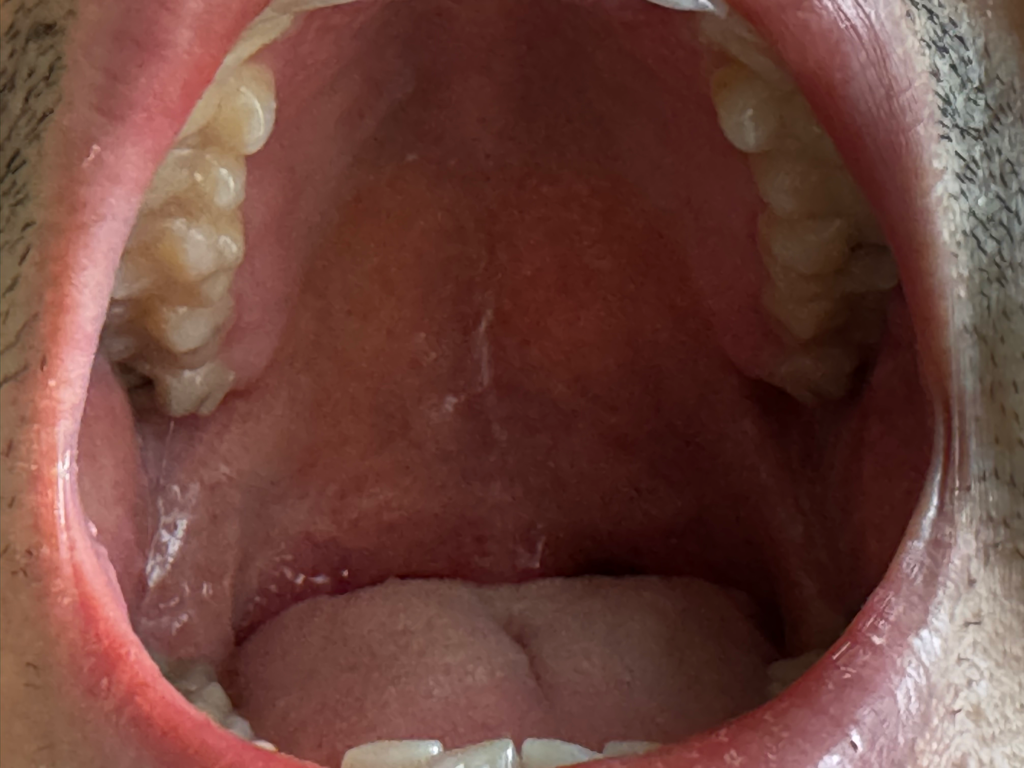

특별하게 이상이 있는 것처럼 보이지는 않습니다

너무 걱정하지 않으셔도 되겠습니다

입 사진에 특별한 이상은 없어서 구강암 가능성은 없을 것으로 판단됩니다. 점막이 약간 까진 것 같은데 자극적이거나 딱딱한 음식만 당분간 피해 보시기 바랍니다.